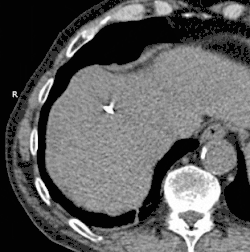

Nerka

Kriochirurgia ma podobne wyniki jak ablacja radiofrekwencyjna w leczeniu raka nerki.[3]